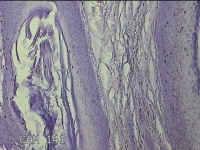

后颈部皮肤结节

性别

男

年龄

45岁

临床诊断

皮肤结节病

一般病史

发现后颈部皮肤结节半年余。

标本名称

大体所见

灰白粉红色组织1.7x0.9x0.3cm一块,表面带梭形皮肤1.7x0.9cm,皮下见结节1.5x1.1cm一个,切开结节呈实性,切面灰白粉红色,质软。

图3